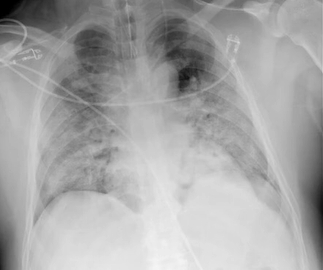

- 호흡기 감염 → 폐렴, 기관지염, 폐농양 (가장 흔한 원인)

염증 반응이 심해지면 혈관이 확장되고 혈압이 급격히 떨어지면서 장기 조직에 산소 공급이 부족해집니다. 이 단계에서는 장기 부전으로 빠르게 진행할 수 있습니다.

이 단계에서는 중환자실 치료가 필요한 경우가 많으며, 치료 지연 시 다장기 부전으로 이어질 위험이 매우 높습니다.

- 산소 치료 또는 인공호흡기 적용 → 조직 산소 공급

- 신장 투석, 간 기능 관리 등 장기 기능 지원